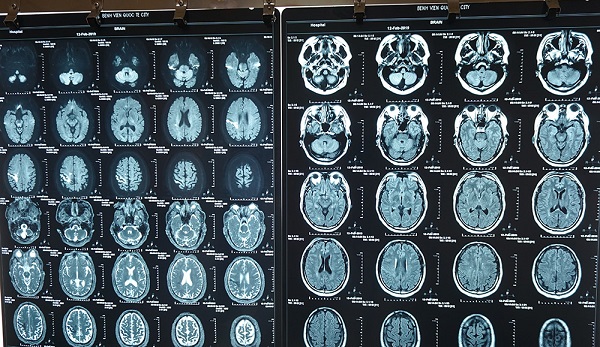

Bệnh nhân được đưa vào Bệnh viện Quốc tế City (TP HCM) cấp cứu ngày 12/2. Kết quả chụp MRI sọ não ghi nhận bệnh nhân bị nhồi máu não cấp giờ thứ 5.

Phim chụp MRI não của bệnh nhân trước khi điều trị.